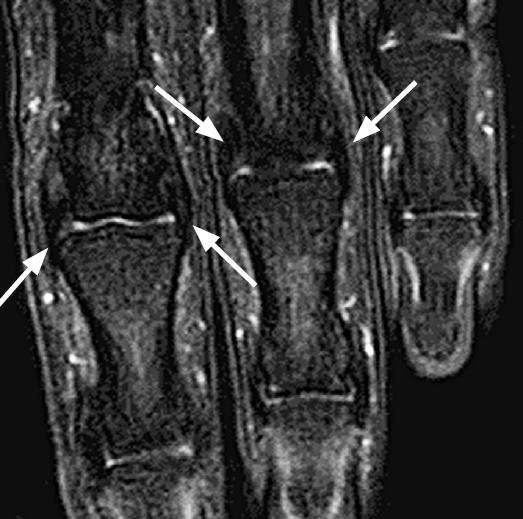

The recent development of advanced high-resolution transducers has enabled the fast, easy, and dynamic ultrasonographic evaluation of small, superficial structures such as the finger. In order to best exploit these advances, it is important to understand the normal anatomy and the basic pathologies of the finger, as exemplified by the following conditions involving the dorsal, volar, and lateral sections of the finger: sagittal band injuries, mallet finger, and Boutonnière deformity (dorsal aspect); flexor tendon tears, trigger finger, and volar plate injuries (volar aspect); gamekeeper's thumb (Stener lesions) and other collateral ligament tears (lateral aspect); and other lesions. This review provides a basis for understanding the ultrasonography of the finger and will therefore be useful for radiologists.

先进的高分辨率换能器的最新发展使得对手指等小而浅表结构进行快速、简便和动态的超声评估成为可能。为了充分利用这些进展,了解手指的正常解剖结构和基本病变非常重要,以下列举了累及手指背侧、掌侧和侧方的一些情况,包括:矢状带损伤、锤状指和纽扣畸形(背侧);屈肌腱撕裂、扳机指和掌板损伤(掌侧);守猎者拇指(斯滕纳损伤)和其他侧副韧带撕裂(外侧);以及其他病变。这篇综述为理解手指的超声检查提供了基础,因此对放射科医生非常有用。